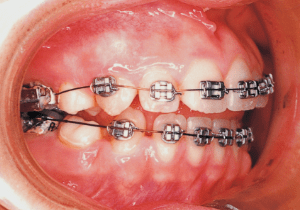

1 Initial Visit 9-2-’85

4 9-2-’85 At initial visit, molar relationship was a strong Class II.